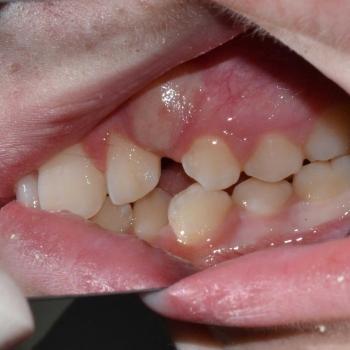

Kíra és édesanyja egy kollegám javaslatára kerestek fel a rögzített fogszabályzó számára legoptimálisabb időszakban, a tejfogak leváltása után, de még a 7-es fog előtörése előtt. Az első konzultáció alkalmával fény derült az alsó és felső fogív nagymértékű torlódására, a jobb felső szemfog kiszorult helyzetére és következményes felső középvonal eltolódására, illetve az enyhe mélyharapásra. A röntgenek kiértékelése után ez a kórkép kiegészült az alsó és felső metszőfogak hátradőlt pozíciójával, ami a kezelést nagyban megkönnyítette, mert lehetőséget adott mindkét fogív meghosszabbítására, így helynyerésre a torlódott fogazat számára.